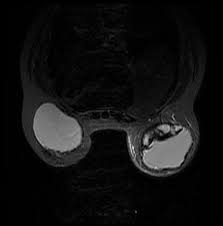

If you have silicone breast implants and suspect that an implant might have ruptured, talk to your plastic surgeon. When a rupture occurs your breast (s) will immediately deflate, usually within a day or two, and breast size will noticeably change. Nevertheless, your body will try to contain any silicone gel seeping in your breast tissue by forming a scar tissue around it, called "granulomas" or "siliconoma". Rupture can also cause capsular contracture. The relationship of free silicone to development or progression of disease is unknown. With silicone gel implants, you aren't able to physically see the appearance of a ruptured implant, whereas with saline implants, you will see a deflated breast with implant rupture. An imaging test, such as an mri or ultrasound, can show whether the implant has ruptured. What are the dangers of silicon? What is the life expectancy of silicone breast implants? Apr 01, 2019 · however, some may remain around the ruptured implant, and this can cause the fluid to change color. What are the risks of silicone implants? Silicone implant rupture that doesn't cause any noticeable symptoms is known as "silent rupture.". This makes is much more difficult to detect a rupture.

With silicone gel implants, you aren't able to physically see the appearance of a ruptured implant, whereas with saline implants, you will see a deflated breast with implant rupture. Light, clear fluid usually signals that the ruptured occurred within a month. Nov 14, 2013 · silicone breast implants can leak but do not deflate quickly the way saline implants do because the silicone gel is designed to stay in place when a leak occurs. An imaging test, such as an mri or ultrasound, can show whether the implant has ruptured. Changes in size or shape.